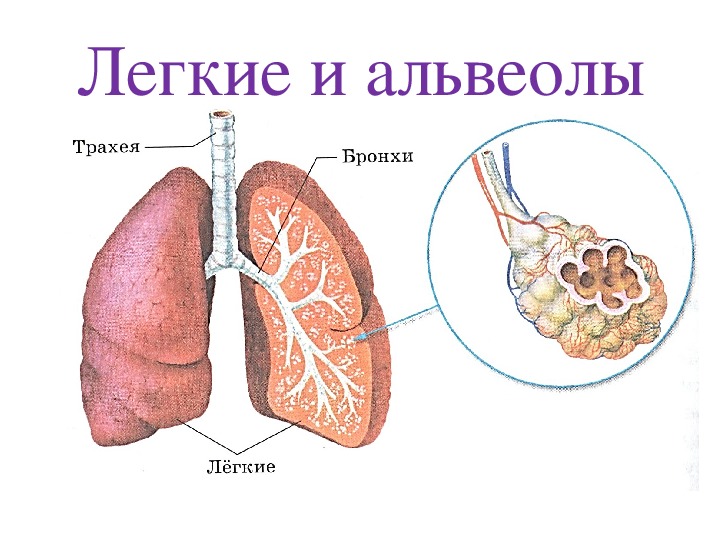

Здоровье дыхательной системы: бронхи и легкие

Раздел: Светлые идеи